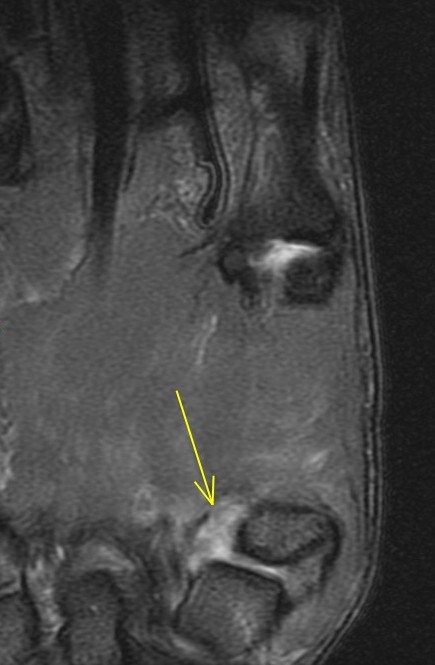

26 y/o crashed on a skateboard.

Patient has torn the deep anterior oblique ligament (beak), and sprained the superficial anterior oblique ligament, posterior oblique ligament and first intermetacarpal ligament. Also a sprain of the dorsoradial ligament. The joint has reduced but the patient related that he can slip it in and out easily. First images are from a dedicated thumb exam and the last image is from the wrist exam.

trapeziometacarpal dislocation